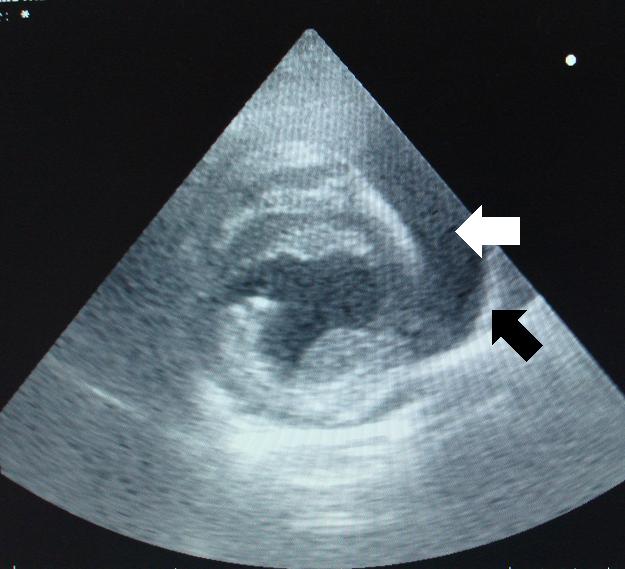

Na tomto sonografickém snímku je zachycena volná nitrobřišní tekutina (černě zbarvená plocha) a v ní plovoucí klička tenkého střeva.

Hemoperikard-SONO břicha-peritoneální efuze2

Nejklíčovějším u tohoto případu bylo ultrasonografické vyšetření srdce. Toto vyšetření nám odhalilo, že  mezi samotným srdcem a osrdečníkem (vakem, který obaluje srdce) se hromadí abnormální množství tekutiny, která v této oblasti za normálních okolností nemá co dělat. Na následujících snímcích je vidět srdce (pravá a levá srdeční komora), kolem kterého je tmavý lem tekutiny (bílé šipky). Ta je od okolí ohraničena světlým (hyperechogenním) lemem - osrdečníkem (černé šipky).

Echokardiografie-perikardiální efuze1

Echokardiografie-perikardiální efuze2